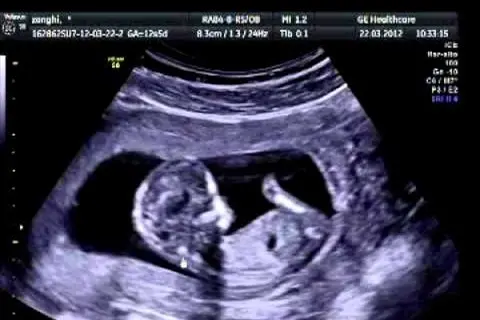

Tra l’altro a quel tempo non c’erano le ecografie e oggi chiunque, a partire dai giovani, possono vedere che dentro quel grembo prima dei tre mesi c’è una vita in carne e ossa: un cuoricino che batte, sangue, cervello, anima. E invece si stravolgono le parole del Papa per portare avanti il proprio sterile totalitarismo libertario che vorrebbe imporre di spegnere la voce di quei medici che si rifiutano di mettere fine a una vita nascente.